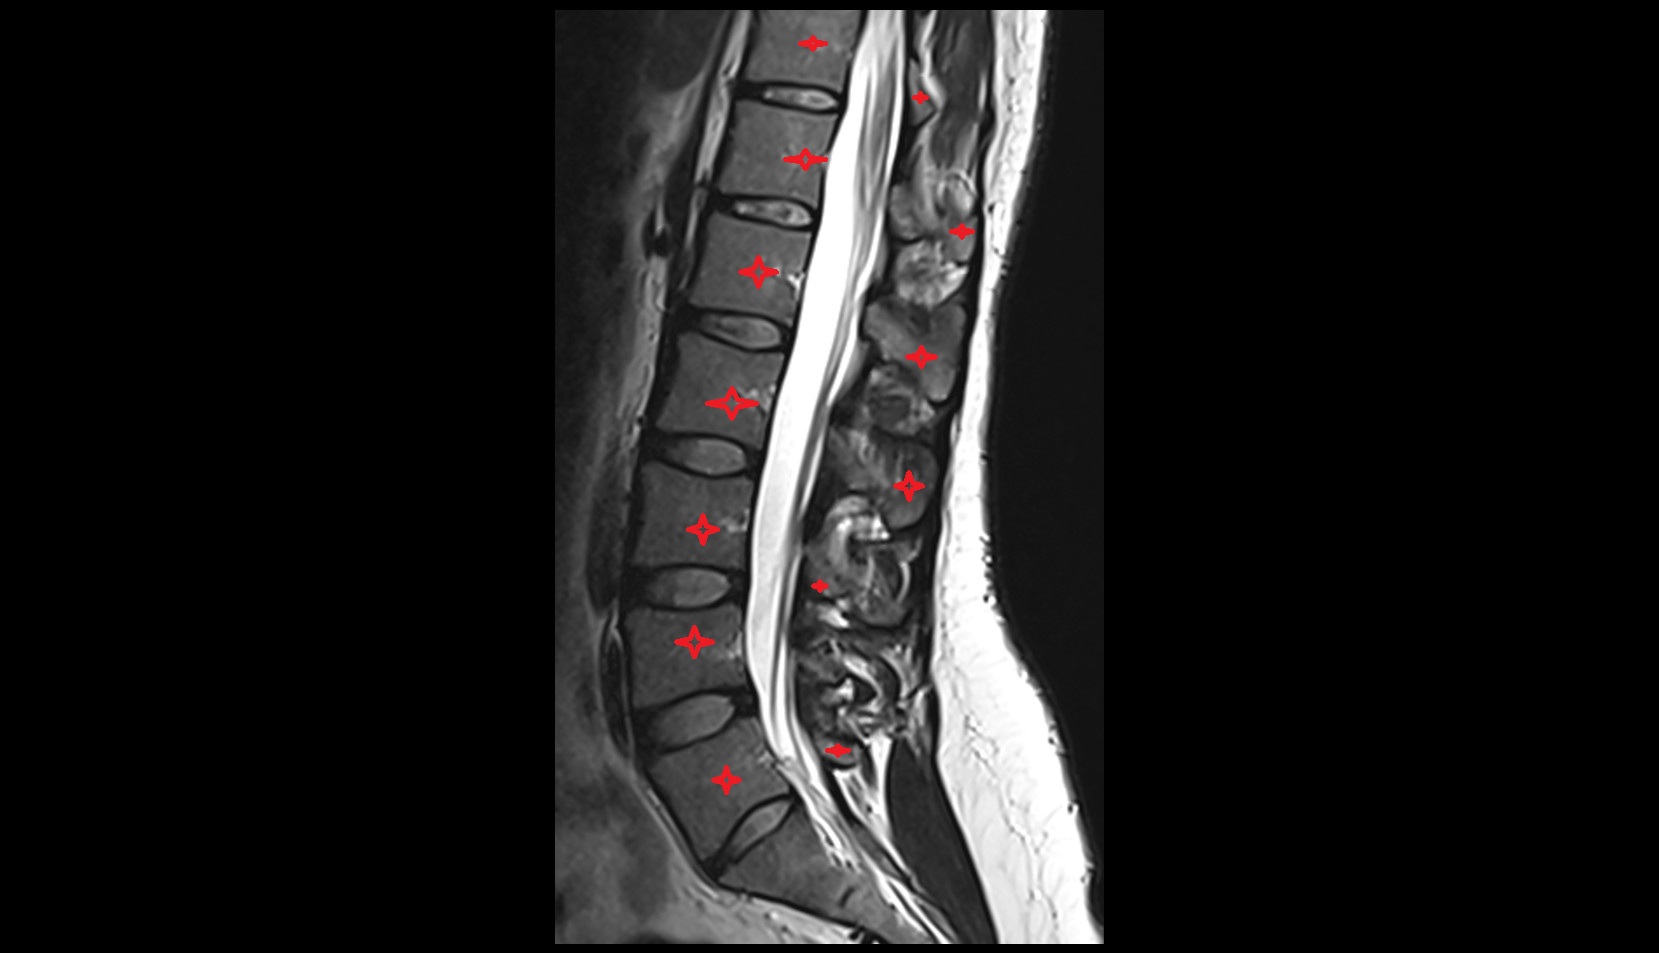

- Cauda equina

- Conus medullaris

- Traversing nerve root of spinal nerve

- Exiting nerve root of spinal nerve

- L4–L5 Intervertebral Disc

- L3–L4 Intervertebral Disc

- L2–L3 Intervertebral Disc

- L1–L2 Intervertebral Disc

- Spinal dura mater

- Spinal epidural space